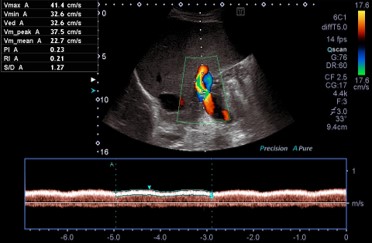

Ultraschalluntersuchungen / Sonografie

Ultraschalluntersuchungen des Bauchraumes

Konventionelle Sonografie

Farbkodierte Duplexsonografie

Ultraschalluntersuchungen der Gefäße

Vorsorge Bauchaortenaneurysma

Scherwellenelastographie der Leber (2D, Point-shear-wave) [IGeL]